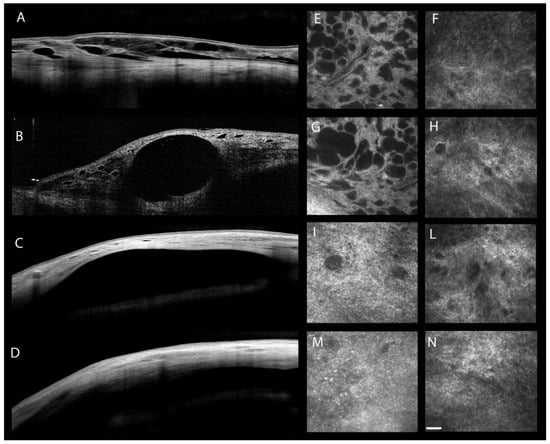

| Ciancaglini M. et al. [88] | 2008 | IVCM a AS-OCT j | POAG e PXG f | Trabeculectomy | |

| Baiocchi S. et al. [85] | 2020 | IVCM a | POAG e | XEN 45 gel stent implant Trabeculectomy | |

| Sacchi M. et al. [98] | 2020 | AS-OCT j IVCM a | POAG e PXG f NTG g | XEN 45 gel stent implant Trabeculectomy | |

- Ciancaglini, M.; Carpineto, P.; Agnifili, L.; Nubile, M.; Lanzini, M.; Fasanella, V.; Mastropasqua, L. Filtering bleb functionality: A clinical, anterior segment optical coherence tomography and in vivo confocal microscopy study. J. Glaucoma 2008, 17, 308–317. [Google Scholar] [CrossRef]

- Sacchi, M.; Agnifili, L.; Brescia, L.; Oddone, F.; Villani, E.; Nucci, P.; Mastropasqua, L. Structural imaging of conjunctival filtering blebs in XEN gel implantation and trabeculectomy: A confocal and anterior segment optical coherence tomography study. Graefes Arch. Clin. Exp. Ophthalmol. 2020, 258, 1763–1770. [Google Scholar] [CrossRef]